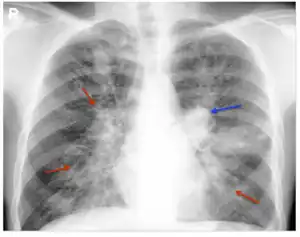

| Chest Xray of allergic bronchopulmonary aspergillosis showing left-sided perihilar opacity (blue arrow) along with non-homogeneous infiltrates (transient pulmonary infiltrates indicated by red arrows) in all zones of both lung fields | |